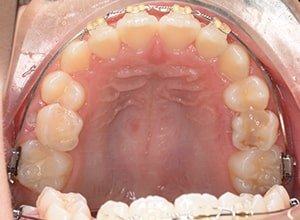

| 使用装置 | 0.018" × 0.025" standard edgewise | ||||||

| 保定装置 | 上顎 Begg Type Retainer | ||||||

| 批評・予后 | 右下5及び7の萌出前に右下6を整直させることによって、右下5の自然萌出が可能となり正常咬合への咬合誘導が行えたと思う。 |

| リスク | 通院間隔が長くなったり顎間ゴムの協力が得られないと予定の治療期間より延長したり仕上がりが不十分になる恐れがあります。 ブラッシングを怠ると虫歯のリスクが高くなります。 |